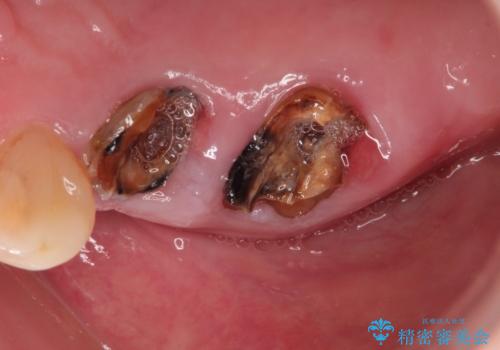

右上のかぶせ物がとれてしまい、残った根っこも虫歯になってしまっていました。

また右下の歯も虫歯と歯周病により長く使用するには難しい状態でした。

右の上下の歯を抜歯してインプラントを埋入して、かぶせ物を装着する計画としました。